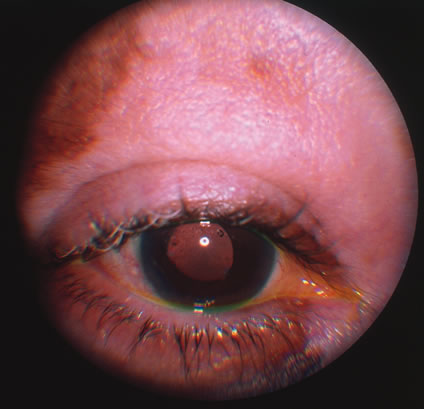

In primary ocular HSV infections, a severe follicular conjunctivitis with regional adenopathy is present. Vesicles may appear on the eyelid skin or lid margin, producing blepharitis (Fig. 3). Corneal involvement initially takes the form of a superficial punctate keratitis, which may progress to dendritic or geographic ulceration. Stromal infiltrates and uveitis are less common and relatively mild in primary disease. In uncomplicated cases, lesions usually heal completely in 2 to 3 weeks without scarring. Most cases of ocular HSV are recurrences. Recrudescent ocular herpes may take the form of dendritic or geographic ulcers, recurrent erosions, interstitial or disciform stromal keratitis, and anterior uveitis.3 HSV may also be an agent of retinitis and acute retinal necrosis (Fig. 4).